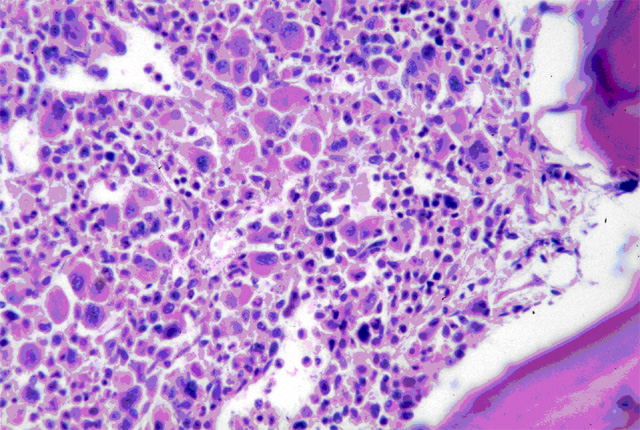

| Médula Osea |

Células Madre Mesenquimales (CMM).

Las CMM son células estromales multipotentes que pueden ser aisladas o recuperadas de numerosos tejidos incluyendo médula ósea, músculo esquelético, fluido amniótico y tejido graso, y son capaces de convertirse en cartílago, hueso, neuronas, músculo y otros tejidos del cuerpo humano.